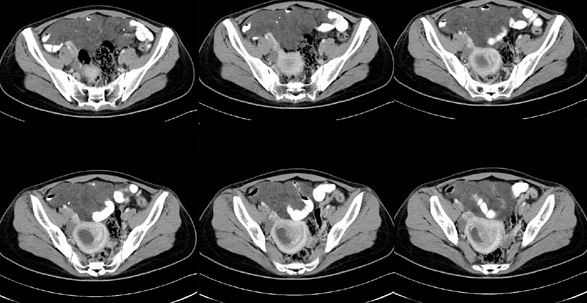

女性,28岁,停经3月,腹部膨隆1月,产前检查发现腹部占位

{肿块中心ct值27hu,增强后,动脉期、门脉期均无明显强化)

患者手术病理:腹腔囊性淋巴管瘤,象这样充满整个腹腔的的确很少见